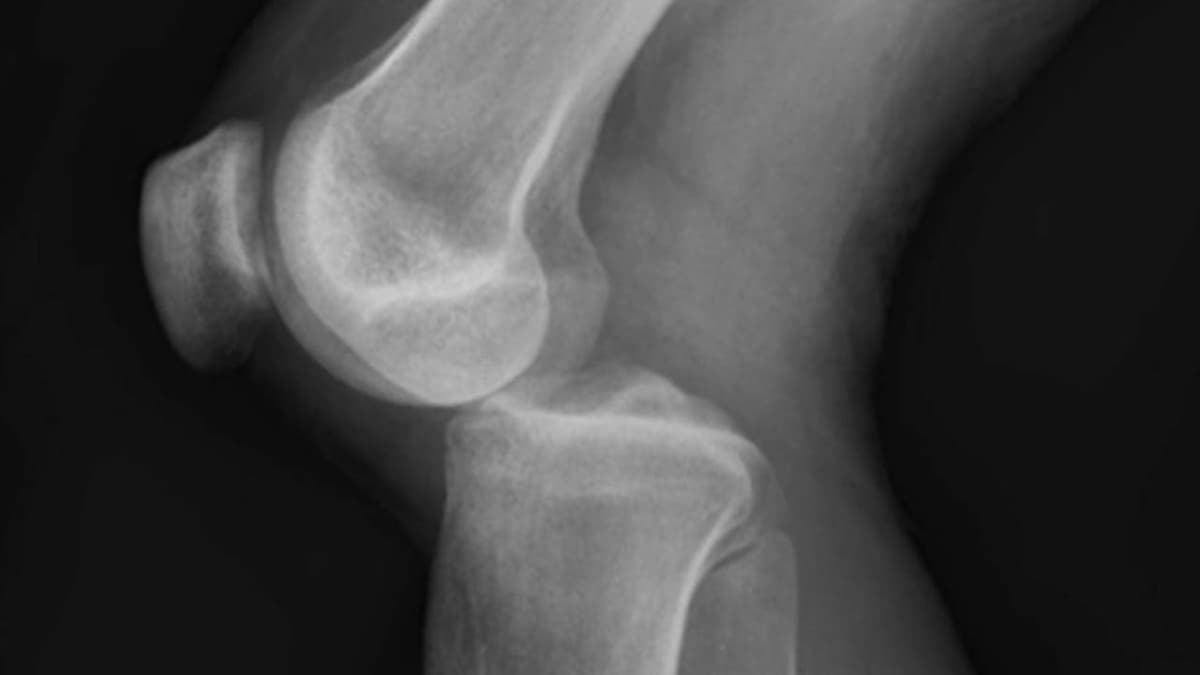

Những điều bạn cần biết về trật khớp háng

Trật khớp háng là một tình trạng y tế nghiêm trọng khi đầu xương đùi bị lệch khỏi hốc khớp háng. Đây là một chấn thương phổ biến trong các tai nạn giao thông, tai nạn thể thao hoặc các tai nạn sinh hoạt hàng ngày. Cùng tìm hiểu để biết nguyên nhân, triệu chứng […]